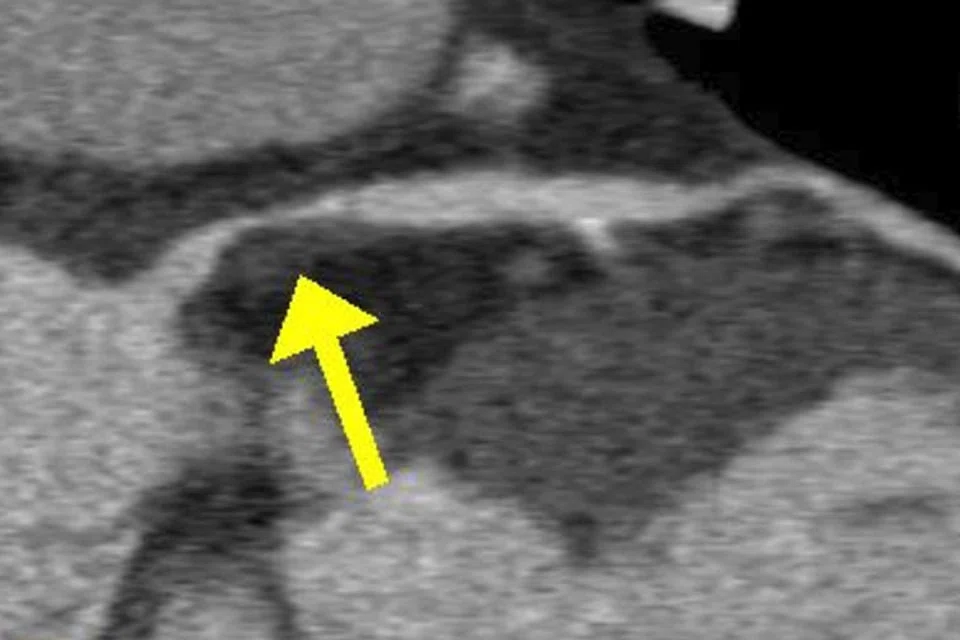

Heart failure and its aetiology can be assessed by echocardiogram, magnetic resonance imaging of the heart and radionuclide myocardial perfusion imaging. CT coronary angiogram is useful to assess the presence of coronary artery disease non-invasively. Invasive coronary angiography can ultimately assess the presence or absence of significant coronary artery disease.